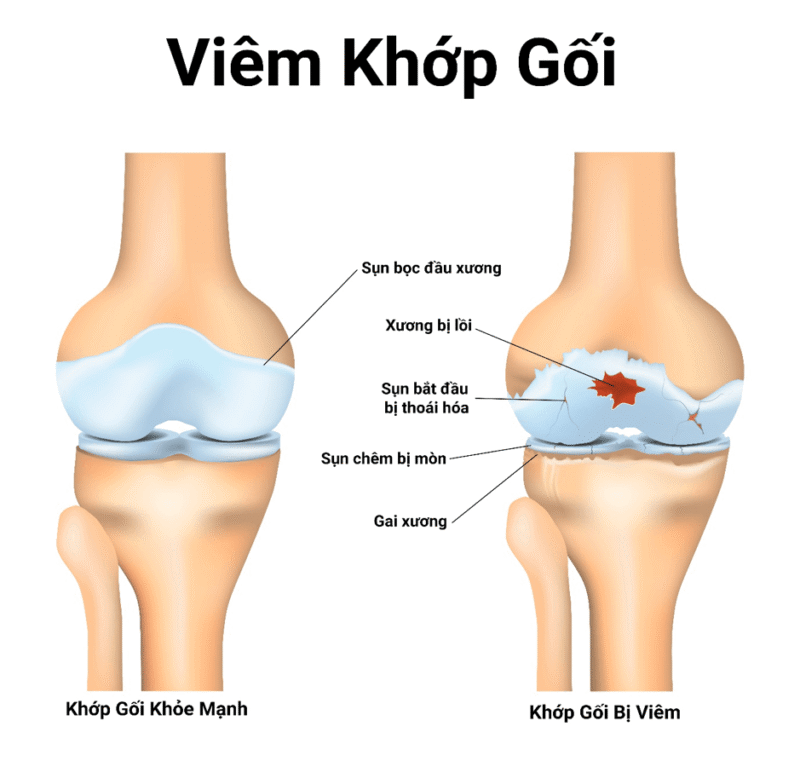

Trà dịch vụ khớp gối là tình trạng dịch vụ tăng cường bất thường trong hộp gối. Bình thường, khớp gối luôn có một dịch vụ phù hợp nhất để bôi trơn và nuôi dưỡng sụn khớp. Khi khớp bị tổn thương hoặc viêm, lượng dịch này ngày càng tăng, gây ngứa và đau.

Phù hợp với chức năng giảm ma sát giữa các miếng thịt, giúp vận động trơn tru và hấp thụ lực tác động khi đi lại, chạy nhảy. Khi trận đấu tăng cường, áp dụng sức mạnh trong trận đấu tăng lên, dẫn đến cơn đau và chế độ vận hành.

Thoái hóa khớp gối là bệnh lý mạn tính thường gặp ở người cao tuổi. Khi miếng khớp bị mòn mòn, các phản ứng viêm xảy ra trong trận đấu, làm tăng lượng dịch khớp và gây tràn dịch.

Các bệnh lý viêm khớp như viêm khớp dạng thấp hoặc viêm do nhiễm trùng nhiễm khuẩn có thể gây tràn dịch khớp gối. Trong những trường hợp này, giao dịch tràn thường đi kèm với sự đau đớn và bối cảnh khó khăn.